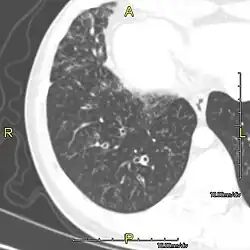

CT image showing dilated and thickened medium-sized airways (bronchiectasis) in a patient with Kartagener syndrome

Around 80% of people with primary ciliary dyskinesia experience respiratory problems beginning within a day of birth. Many have a collapsed lobe of the lung and blood oxygen low enough to require treatment with supplemental oxygen.[1] Within the first few months of life, most develop a chronic mucus-producing cough and runny nose.[1] The main consequence of impaired ciliary function is reduced or absent mucus clearance from the lungs, and susceptibility to chronic recurrent respiratory infections, including sinusitis, bronchitis, pneumonia, and otitis media. Progressive damage to the respiratory system is common, including progressive bronchiectasis beginning in early childhood, and sinus disease (sometimes becoming severe in adults). However, diagnosis is often missed early in life despite the characteristic signs and symptoms.[2] In males, immotility of sperm can lead to infertility, although conception remains possible through the use of in vitro fertilization, there also are reported cases where sperm were able to move.[8] Trials have also shown that there is a marked reduction in fertility in females with Kartagener's syndrome due to dysfunction of the oviductal cilia.[9]